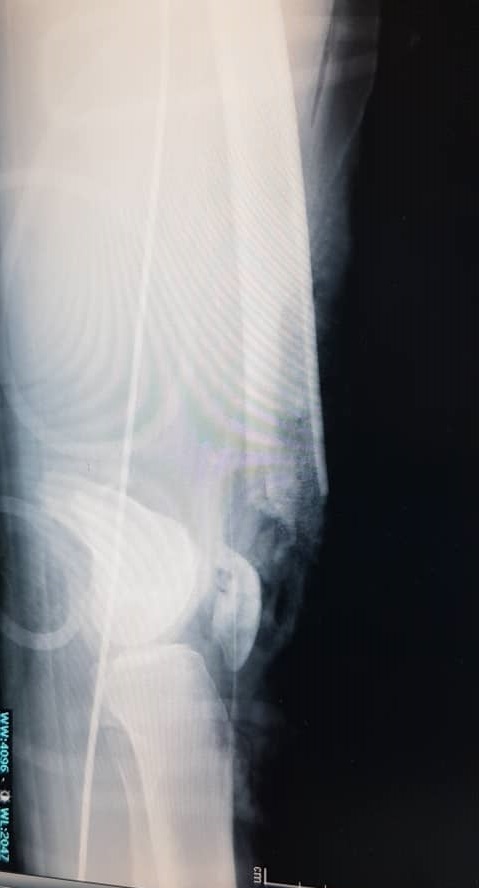

A 22-year-old man presented to our hospital in December 2020 following a motor vehicle accident. The patient had no significant medical, family, or allergy history. He worked in a metal factory and occasionally smoked. The sustained injuries included a closed fracture of the right neck of the femur, an open right supracondylar femur fracture (Gustilo 3C), and an open midshaft fracture of the right tibia (Gustilo 2) (Figures 1, 2, and 3).